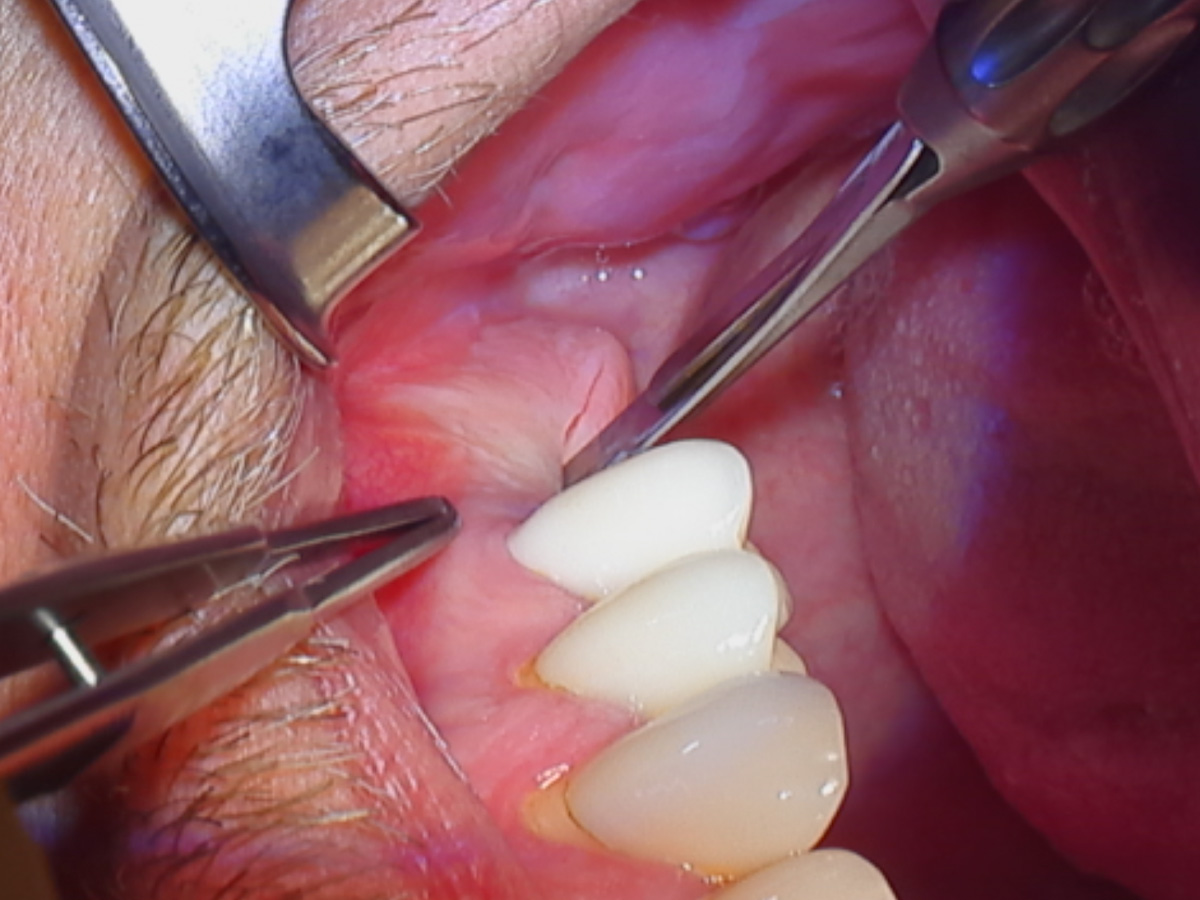

Abbildung 2

Zugangsschnittführung zur Kieferhöhle.